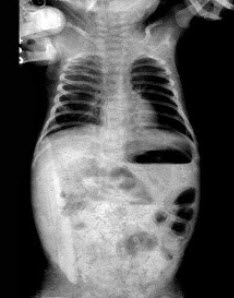

77、单项选择题

男婴,4月。腹部涨满,如图所示。最可能的诊断为()

A.小肠闭锁

B.坏死性小肠结肠炎

C.十二指肠闭锁

D.肠套叠

E.肠穿孔